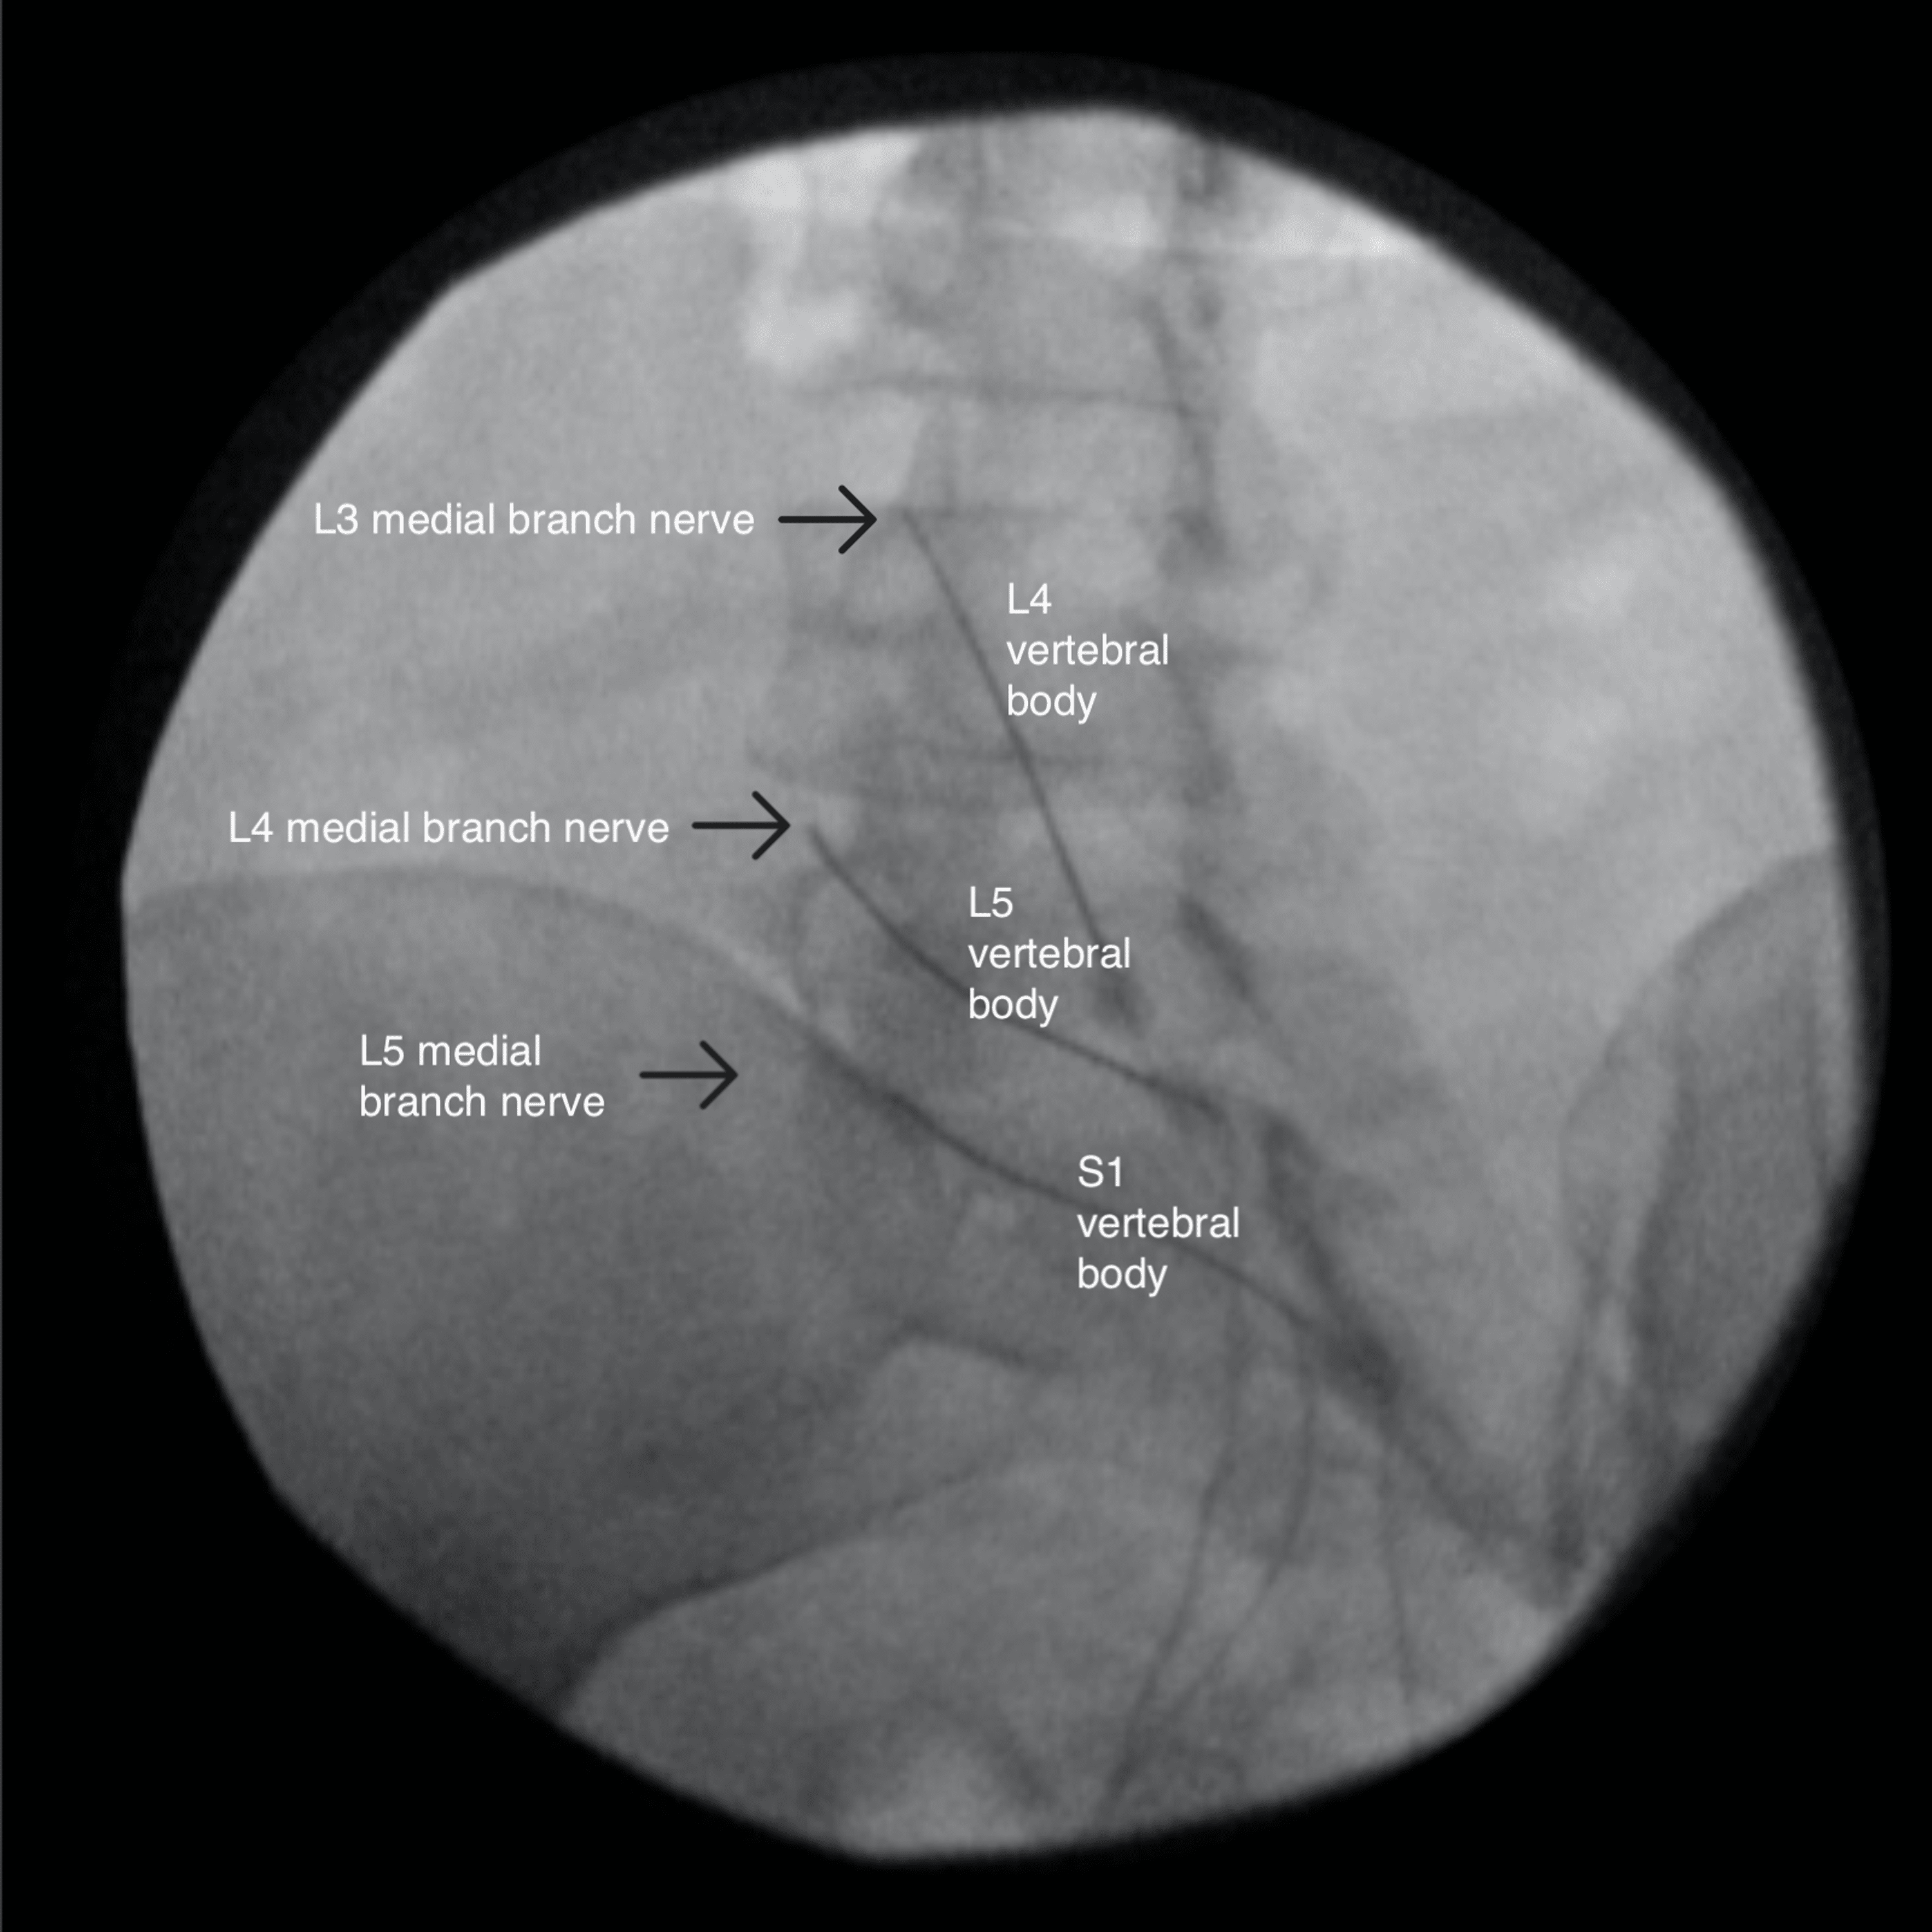

A Radiofrequency ablation at L5 (AP view). Download Scientific Diagram Radiofrequency Ablation Adverse Effects Web the thermal energy associated with radiofrequency ablation leads to tissue. Radiofrequency ablation (rfa) is a minimally invasive procedure that is performed at a doctor’s office or a. Web what are the side effects and risks of radiofrequency ablation (rfa)? During the procedure, you may experience some pain or burning sensation. Web immediately after radiofrequency ablation, the following side effects. Radiofrequency Ablation Adverse Effects.